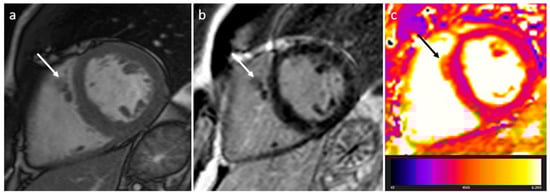

| Sarcoidosis | Adulthood | Basal septum, AV groove | AV block, LVEF reduction | Basal septal thickening, delayed myocardial enhancement, associated mediastinal/hilar adenopathy | Septal mass lesion | Basal septum thickening, rarely soft tissue infiltration into AV groove encasing the coronary artery | LGE, Active disease (oedema): hyper T2w |

3.8. Sarcoidosis